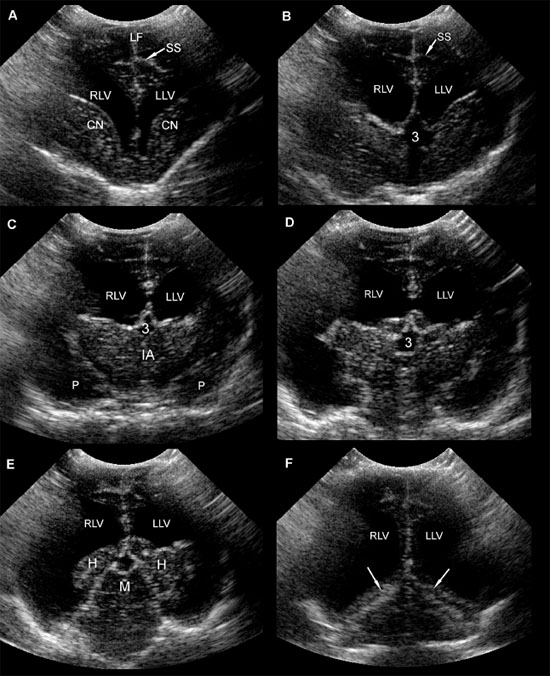

Figure 1.9. Sonograms of a 1-year-old Chihuahua with severe ventriculomegaly. A: Rostral sonogram showing the caudate nuclei and lateral ventricles. B: Sonogram made at the level of the rostral portion of the third ventricle. C: Sonogram made at the level of the thalami. D: Sonogram made at the level of the pituitary gland. Notice the irregularity of the floor of the cranium at this level. E: Sonogram made with the ultrasound beam pointed caudally to display mesencephalon. F: Sonogram showing the osseous tentorium (arrows). 3, third ventricle; CN, caudate nuclei; H, hippocampus; IA, interthalamic adhesion; LF, longitudinal fissure; LLV, left lateral ventricle; M, mesencephalon; P, pyriform lobe; RLV, right lateral ventricle; and SS, splenial sulcus on the left side.

Acquired hydrocephalus can be caused by obstruction at various locations in the ventricular system. Neoplasia, hemorrhage (including intraventricular hemorrhage in the perinatal period), and infection are among the possible causes of obstruction. Location of the obstruction dictates the pattern of dilation of the ventricular system; therefore, a finding of asymmetrical dilation recognizable via ultrasound images can assist in determining the focus of the obstruction. Interference with absorption of CSF from the subarachnoid space into the venous system can cause non-obstructive hydrocephalus. Ex vacuo hydrocephalus is caused by the atrophy or failure of the brain to develop (Ettinger and Feldman 2005).

Several methods have been proposed for evaluating enlarged lateral ventricles on sonograms (Figure 1.10 and Table 1.1). The degree of ventriculomegaly ranges from the ventricles being only slightly enlarged to ventricles occupying most of the brain. Midline structures between the lateral ventricles are intact in some animals, but the lateral ventricles become confluent in others (Figure 1.11).